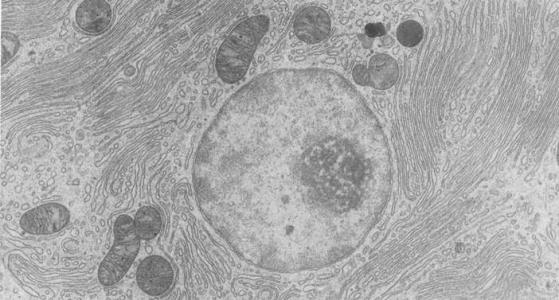

超聲波技術(shù)是工程界、學(xué)術(shù)界公認(rèn)的高新技術(shù)與未來產(chǎn)業(yè)之一。轉(zhuǎn)子泵20世紀(jì)80年代以來,超聲波技術(shù)不斷應(yīng)用于工業(yè)、農(nóng)業(yè)、醫(yī)藥衛(wèi)生等領(lǐng)域。近年來,該技術(shù)隨著物理、電子、機(jī)械、材料學(xué)的長足進(jìn)步及許多邊緣或交叉工業(yè)領(lǐng)域需求的增加而得到迅猛發(fā)展,超聲波技術(shù)在生物學(xué)領(lǐng)域的應(yīng)用涉及到細(xì)胞的豉碎、滅菌,提取胞內(nèi)物質(zhì),增強(qiáng)細(xì)胞內(nèi)酶的生產(chǎn),提高非水相酶催化的均質(zhì)效應(yīng),改善細(xì)胞的壁膜結(jié)構(gòu)以增加通透性以及對液體中固形物或液體濃度的在線檢測等。衛(wèi)生泵適當(dāng)控制超聲波作用的強(qiáng)度和頻率,可使之對工業(yè)微生物產(chǎn)生正面效應(yīng),提髙工業(yè)微生物發(fā)酵過程的效率。液下泵超聲波轉(zhuǎn)化是一種高效的將外源基因?qū)怂拗骷?xì)胞的方法,目前在哺乳動(dòng)物和植中應(yīng)用較多,而在微生物中的應(yīng)用鮮見報(bào)道。油泵